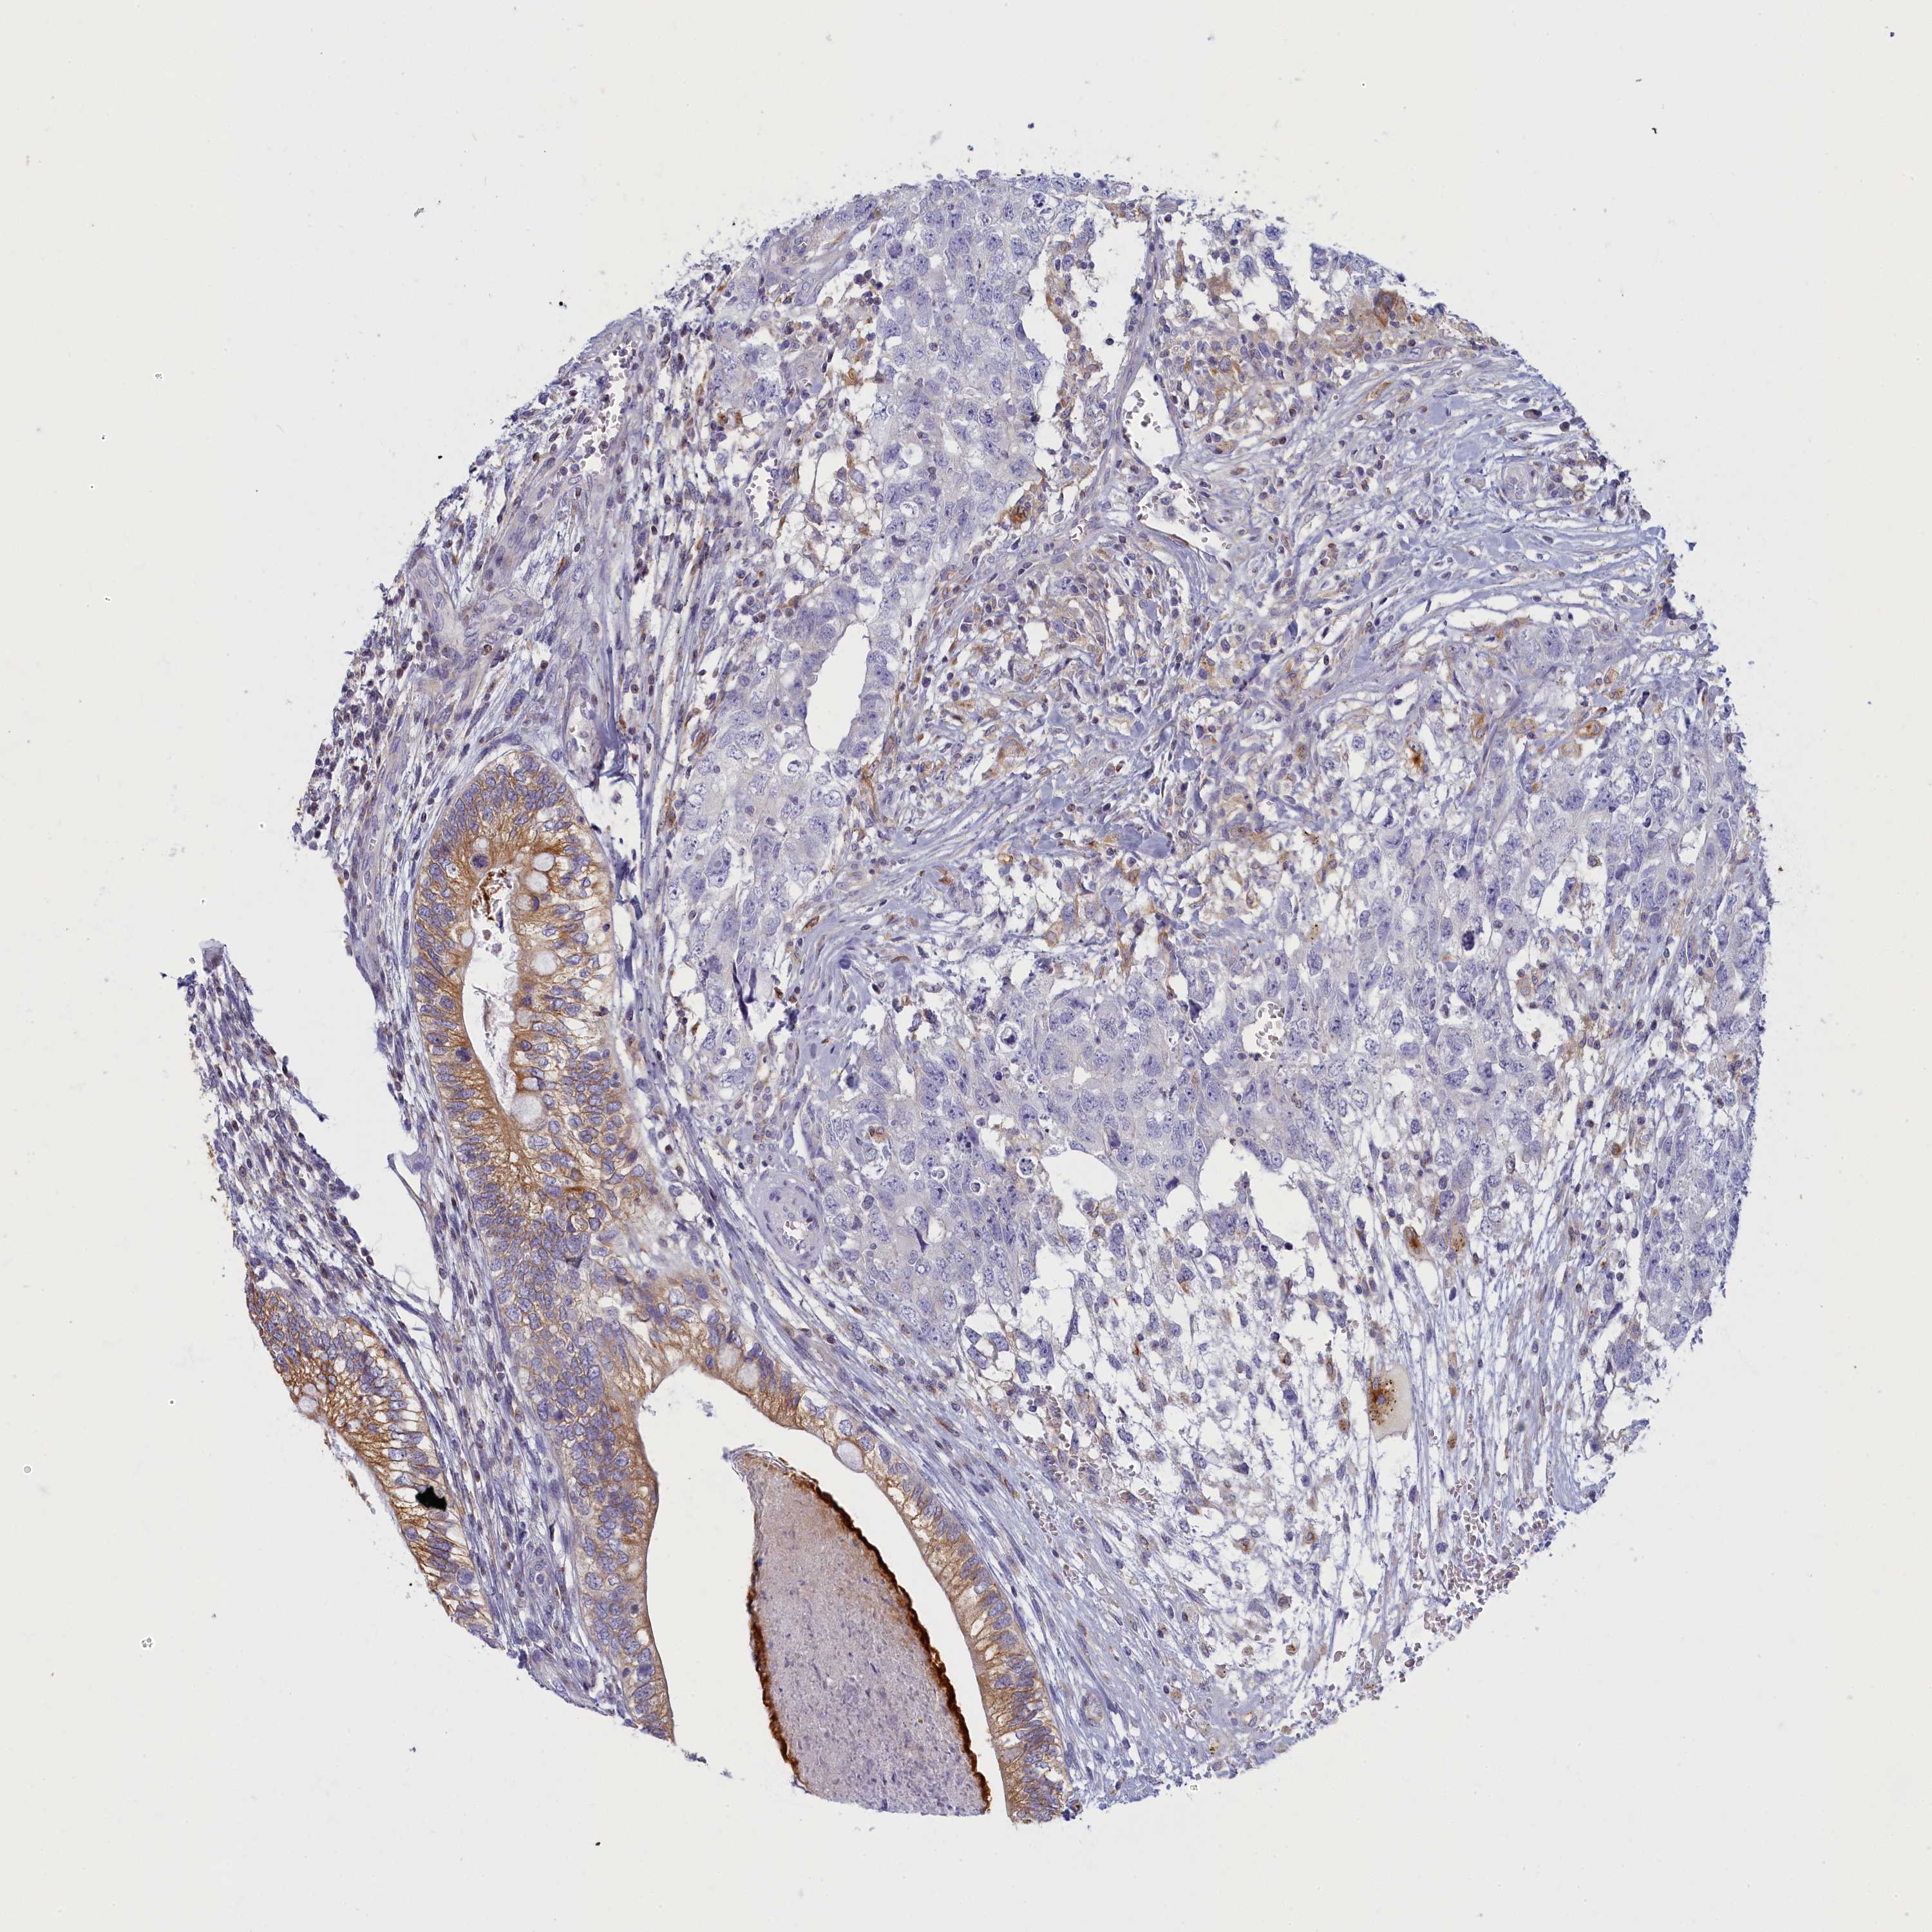

TESTIS CANCER - Protein expressioni

A mouse-over function shows sample information and annotation data. Click on an image to view it in a full screen mode. Samples can be filtered based on level of antibody staining by selecting one or several of the following categories: high, medium, low and not detected. The assay and annotation is described here.

Note that samples used for immunohistochemistry by the Human Protein Atlas do not correspond to samples in the TCGA dataset.

Antibody stainingi

Antibody staining in the annotated cell types in the current human tissue is reported as not detected, low, medium, or high, based on conventional immunohistochemistry profiling in selected tissues. This score is based on the combination of the staining intensity and fraction of stained cells.

Each image is clickable and will lead to virtual microscopy that enables deeper exploration of all samples and also displays staining intensity scores, fraction scores and subcellular localization as well as patient and tissue information for each sample.

Antibody HPA043075

Staining

High

Medium

Low

Not detected

Intensity

Strong

Moderate

Weak

Negative

Quantity

>75%

75%-25%

<25%

None

Location

Nuclear

Cytoplasmic/membranous

Cytoplasmic/membranous,nuclear

Carcinoma, Embryonal, NOS

Seminoma, NOS